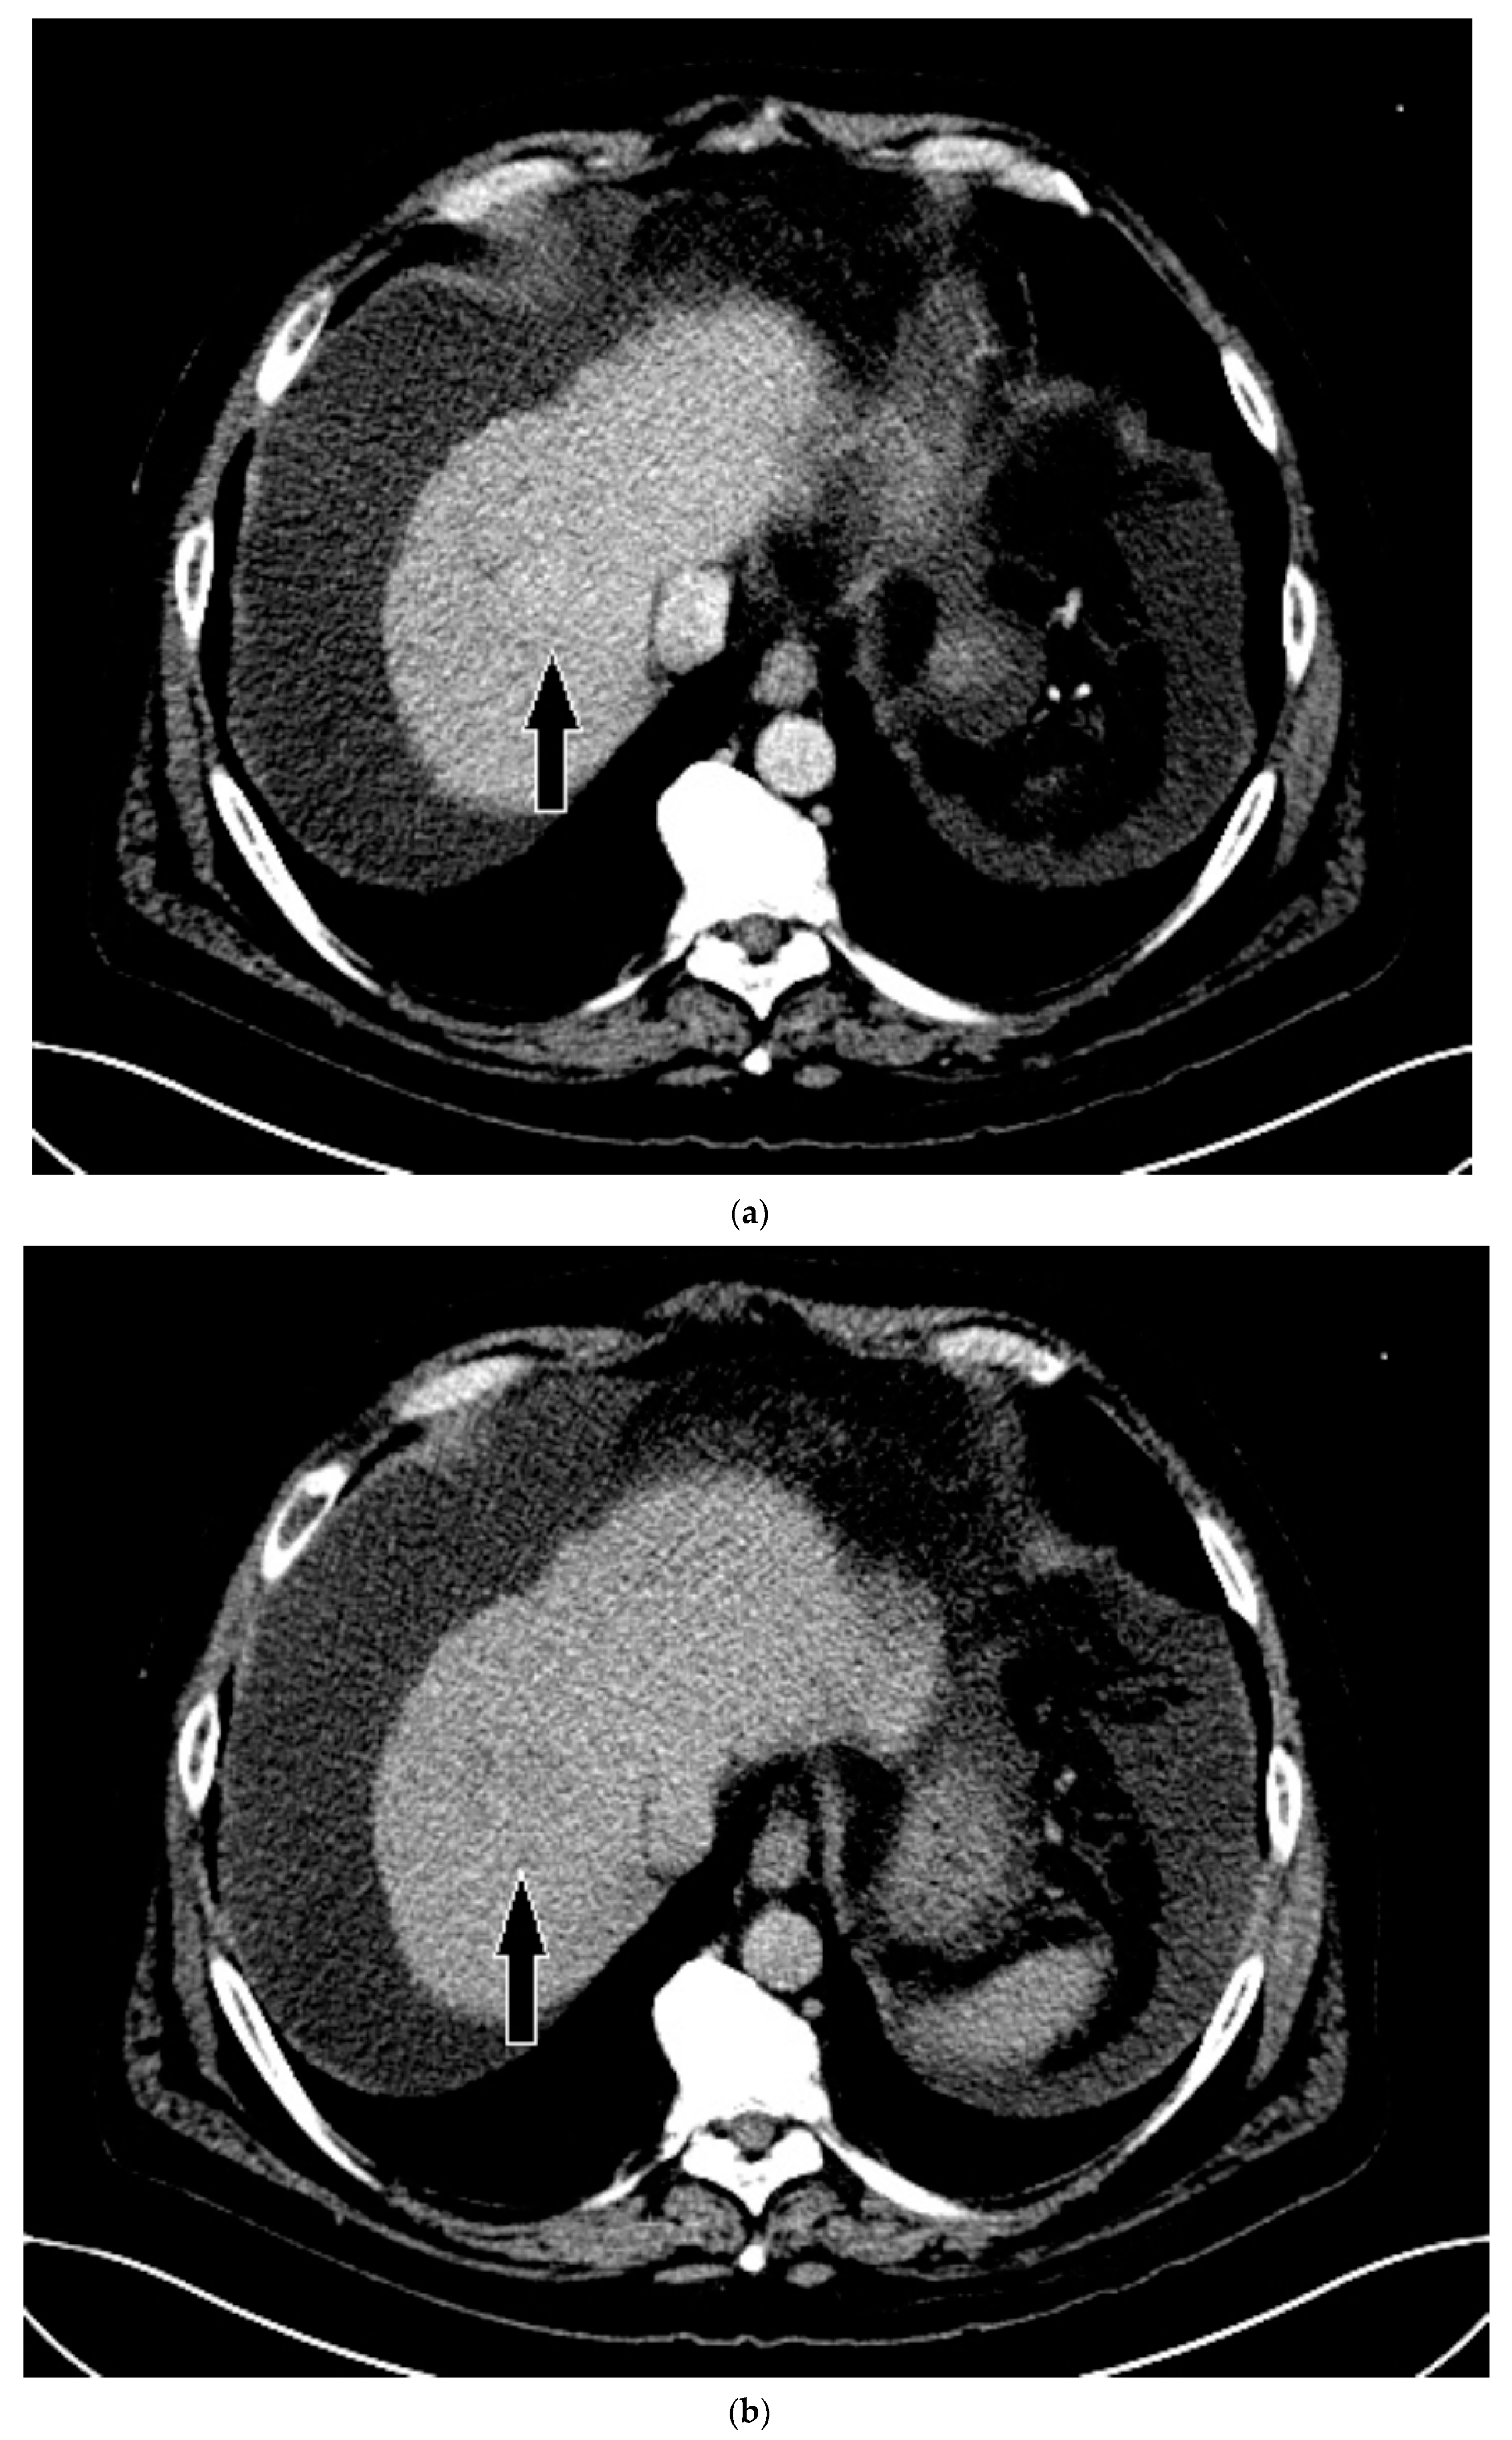

3.3. Case 3